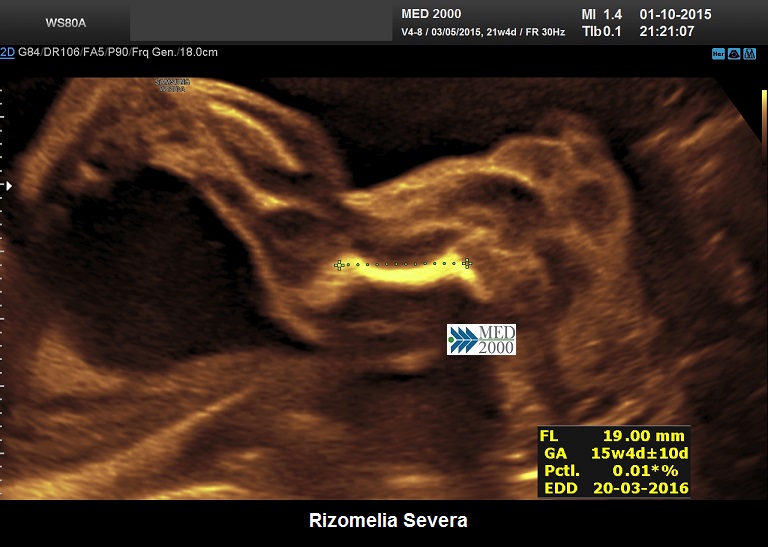

La Displasia Tanatofora tipo 1 è trasmessa con modalità autosomica dominante ed è caratterizzata principalmente da RIZOMELIA SEVERA, FEMORI CORTI (A CORNETTA DI TELEFONO), IPOPLASIA TORACICA SEVERA.

Dal punto di vista ecografico il tratto rizomelico è estremamente ipoplasico, ricurvo e con le metafisi slargate (Femore a Cornetta di Telefono) -  (il riconoscimento del Femore a Cornetta di Telefono rappresenta un segno importantissimo e sufficiente per porre con certezza la diagnosi di Displasia Tanatofora tipo I); vi sono coste corte con ipoplasia toracica e si osserva il classico gradino al passaggio tra torace ipoplasico e addome apparentemente prevalente; vi è in genere macrocrania con bozze frontali prominenti (frontal bossing) e naso a sella. Si associa polidramnios severo.